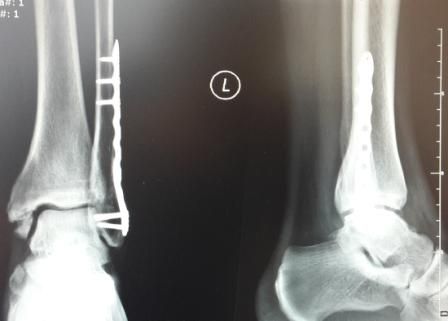

Zdjęcia i filmy